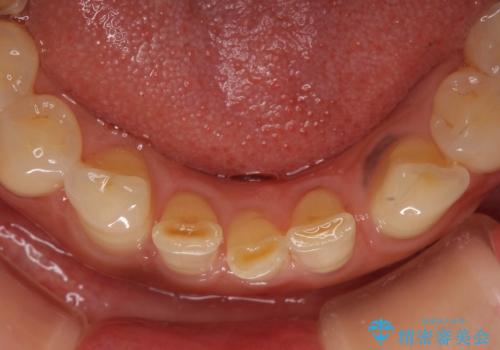

左上の歯は割れてしまっており、抜歯のうえインプラント治療が必要であり、他にも抜歯の必要な歯がある状態でした。

上顎はほぼ全ての歯をセラミッククラウンにて補綴治療を行う必要があるため、気になるデコボコや深い咬み合わせを改善するために下顎と上顎の臼歯部の矯正治療を行うこととしました。

並行して左下にはインプラントを埋入し、矯正治療を終えると同時に補綴治療を行うこととしました。

過蓋咬合(下顎前歯が隠れてしまうほどの深い咬み合わせ)のため、スムーズに歯が動かず矯正治療に時間がかかりましたが、無事に仕上げることができました。